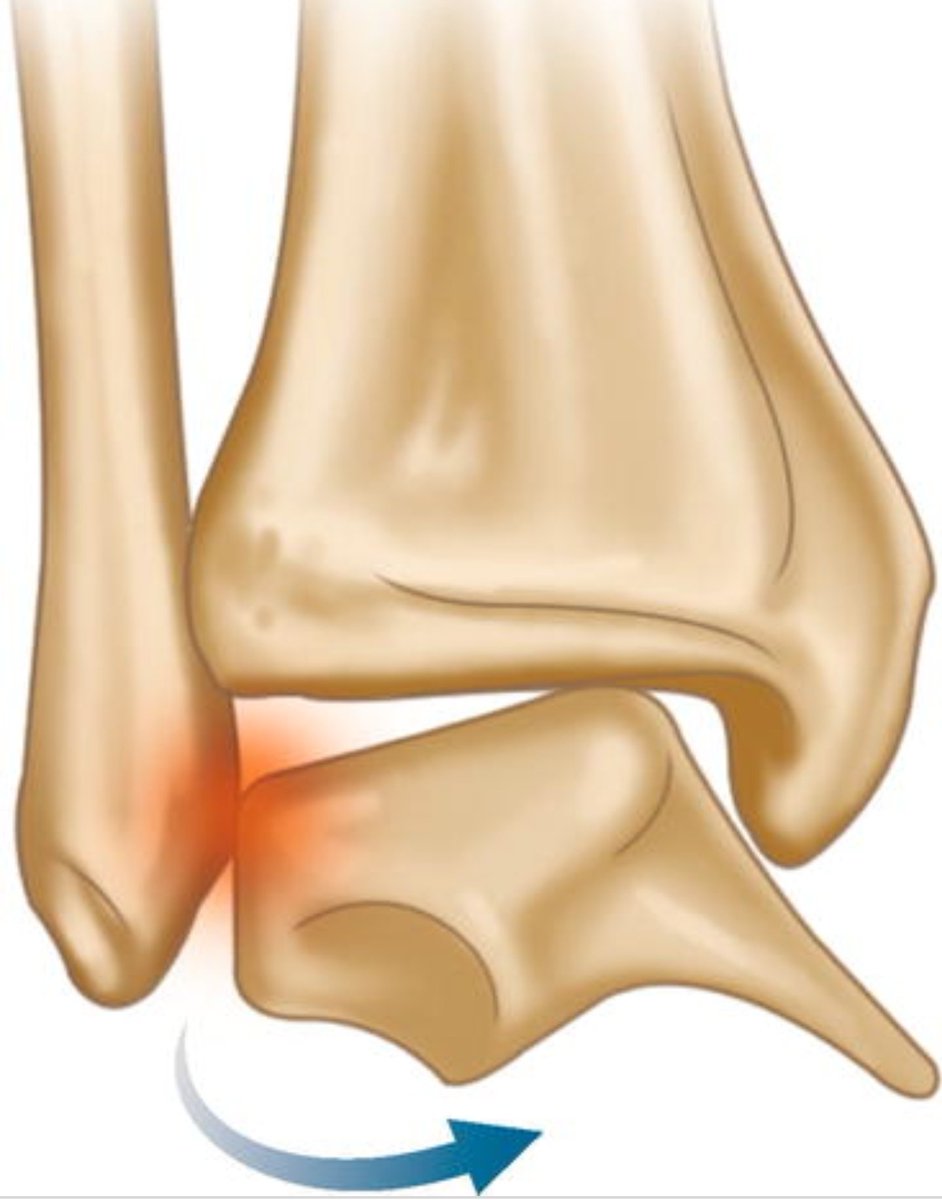

الأسباب:

كسور القدم والكاحل

التواء الكاحل وإصابة الاربطة الجانبية للكاحل

عدم استقرار مزمن الكاحل

تشوهات القدم اللتي تؤدي الى تكرار التواء الكاحل